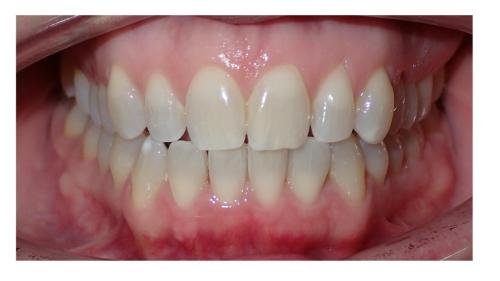

Galería de Sonrisas

large-Cambio magico

large-Cambio labial

large-Adultos -Se puede

large-Sonrisa en adulto

large-Sonrisa Adulto